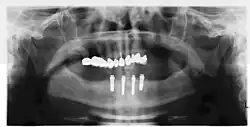

Implant retained fixed bridge or implant supported bridge

An implant supported bridge (or fixed denture) is a group of teeth secured to dental implants so the prosthetic cannot be removed by the user. They are similar to conventional bridges, except that the prosthesis is supported and retained by one or more implants instead of natural teeth. Bridges typically connect to more than one implant and may also connect to teeth as anchor points. Typically the number of teeth will outnumber the anchor points with the teeth that are directly over the implants referred to as abutments and those between abutments referred to as pontics. Implant supported bridges attach to implant abutments in the same way as a single tooth implant replacement. A fixed bridge may replace as few as two teeth (also known as a fixed partial denture) and may extend to replace an entire arch of teeth (also known as a fixed full denture). In both cases, the prosthesis is said to be fixed because it cannot be removed by the denture wearer.[28]